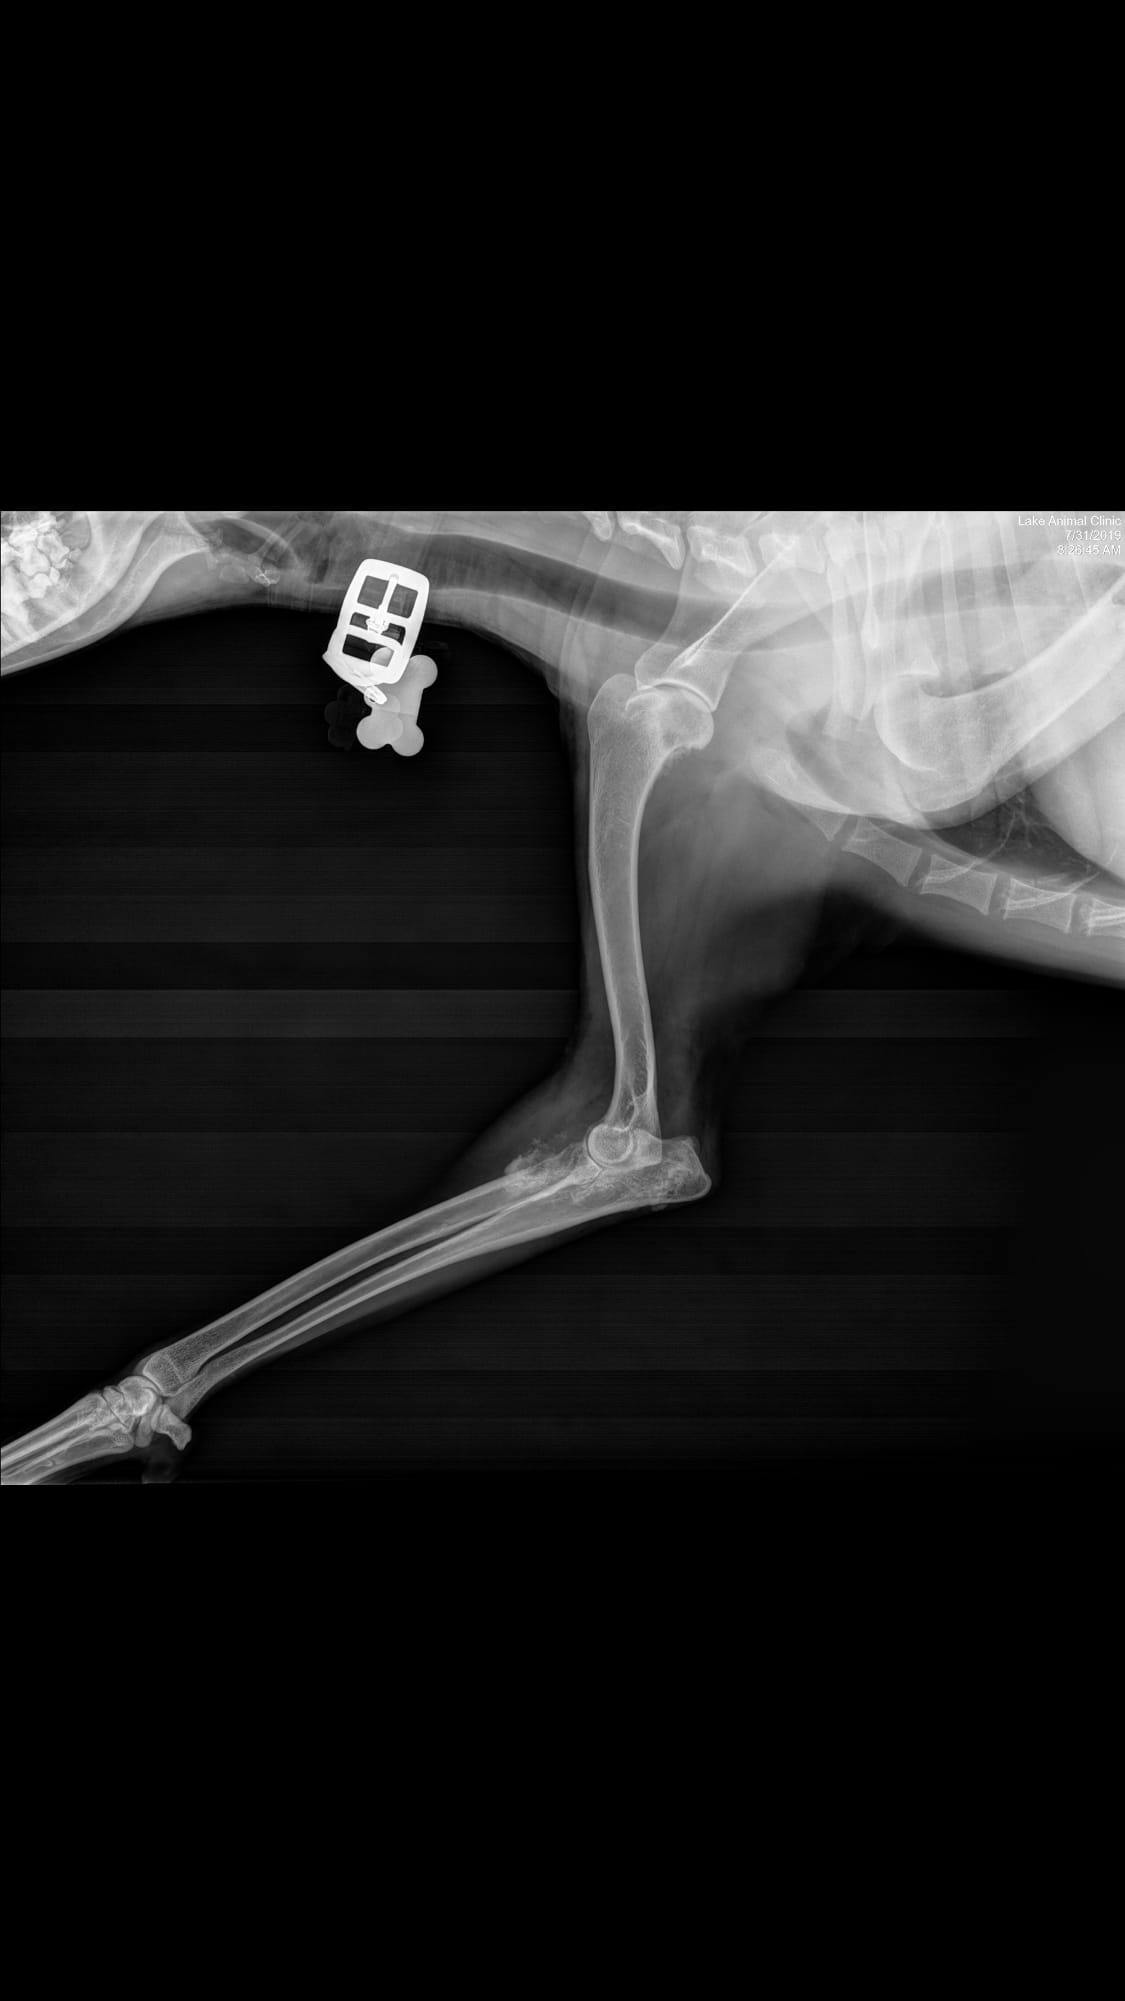

Pet's info: Dog | Goldendoodle | Male | 4 years and 4 months old | 48 lbs

Is this osteosarcoma? My vet said it was but could it be anything else?

Thanks for using Petco Pet Education Center, formerly Petcoach! I would agree that the primary differential based on this radiographs would be a primary bone tumor being osteosarcoma the most common one. However, other things such as a fungal infection depending on the state you live in, is also possible. The next step would be sampling of this lesion via fine needle aspiration or biopsy to confirm the diagnosis. If confirmed, therapy can be discussed at that time. I'm hoping for the best!